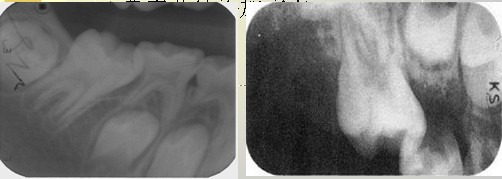

解析: 牙齿异位萌出

牙齿异位萌出的临床表现包括:第一恒磨牙近中边缘嵴阻生于第二乳磨牙远中牙颈下,X线:第二乳磨牙远中根牙颈部吸收区或非典型性吸收,第一恒磨牙近中边缘嵴嵌入;第二乳磨牙间隙开始缩小。治疗措施包括:早期临床观察,钢丝结扎分离,截冠加金属冠修复,拔除第二乳磨牙,导萌器引导恒牙萌出。

解析: 钢丝结扎分离